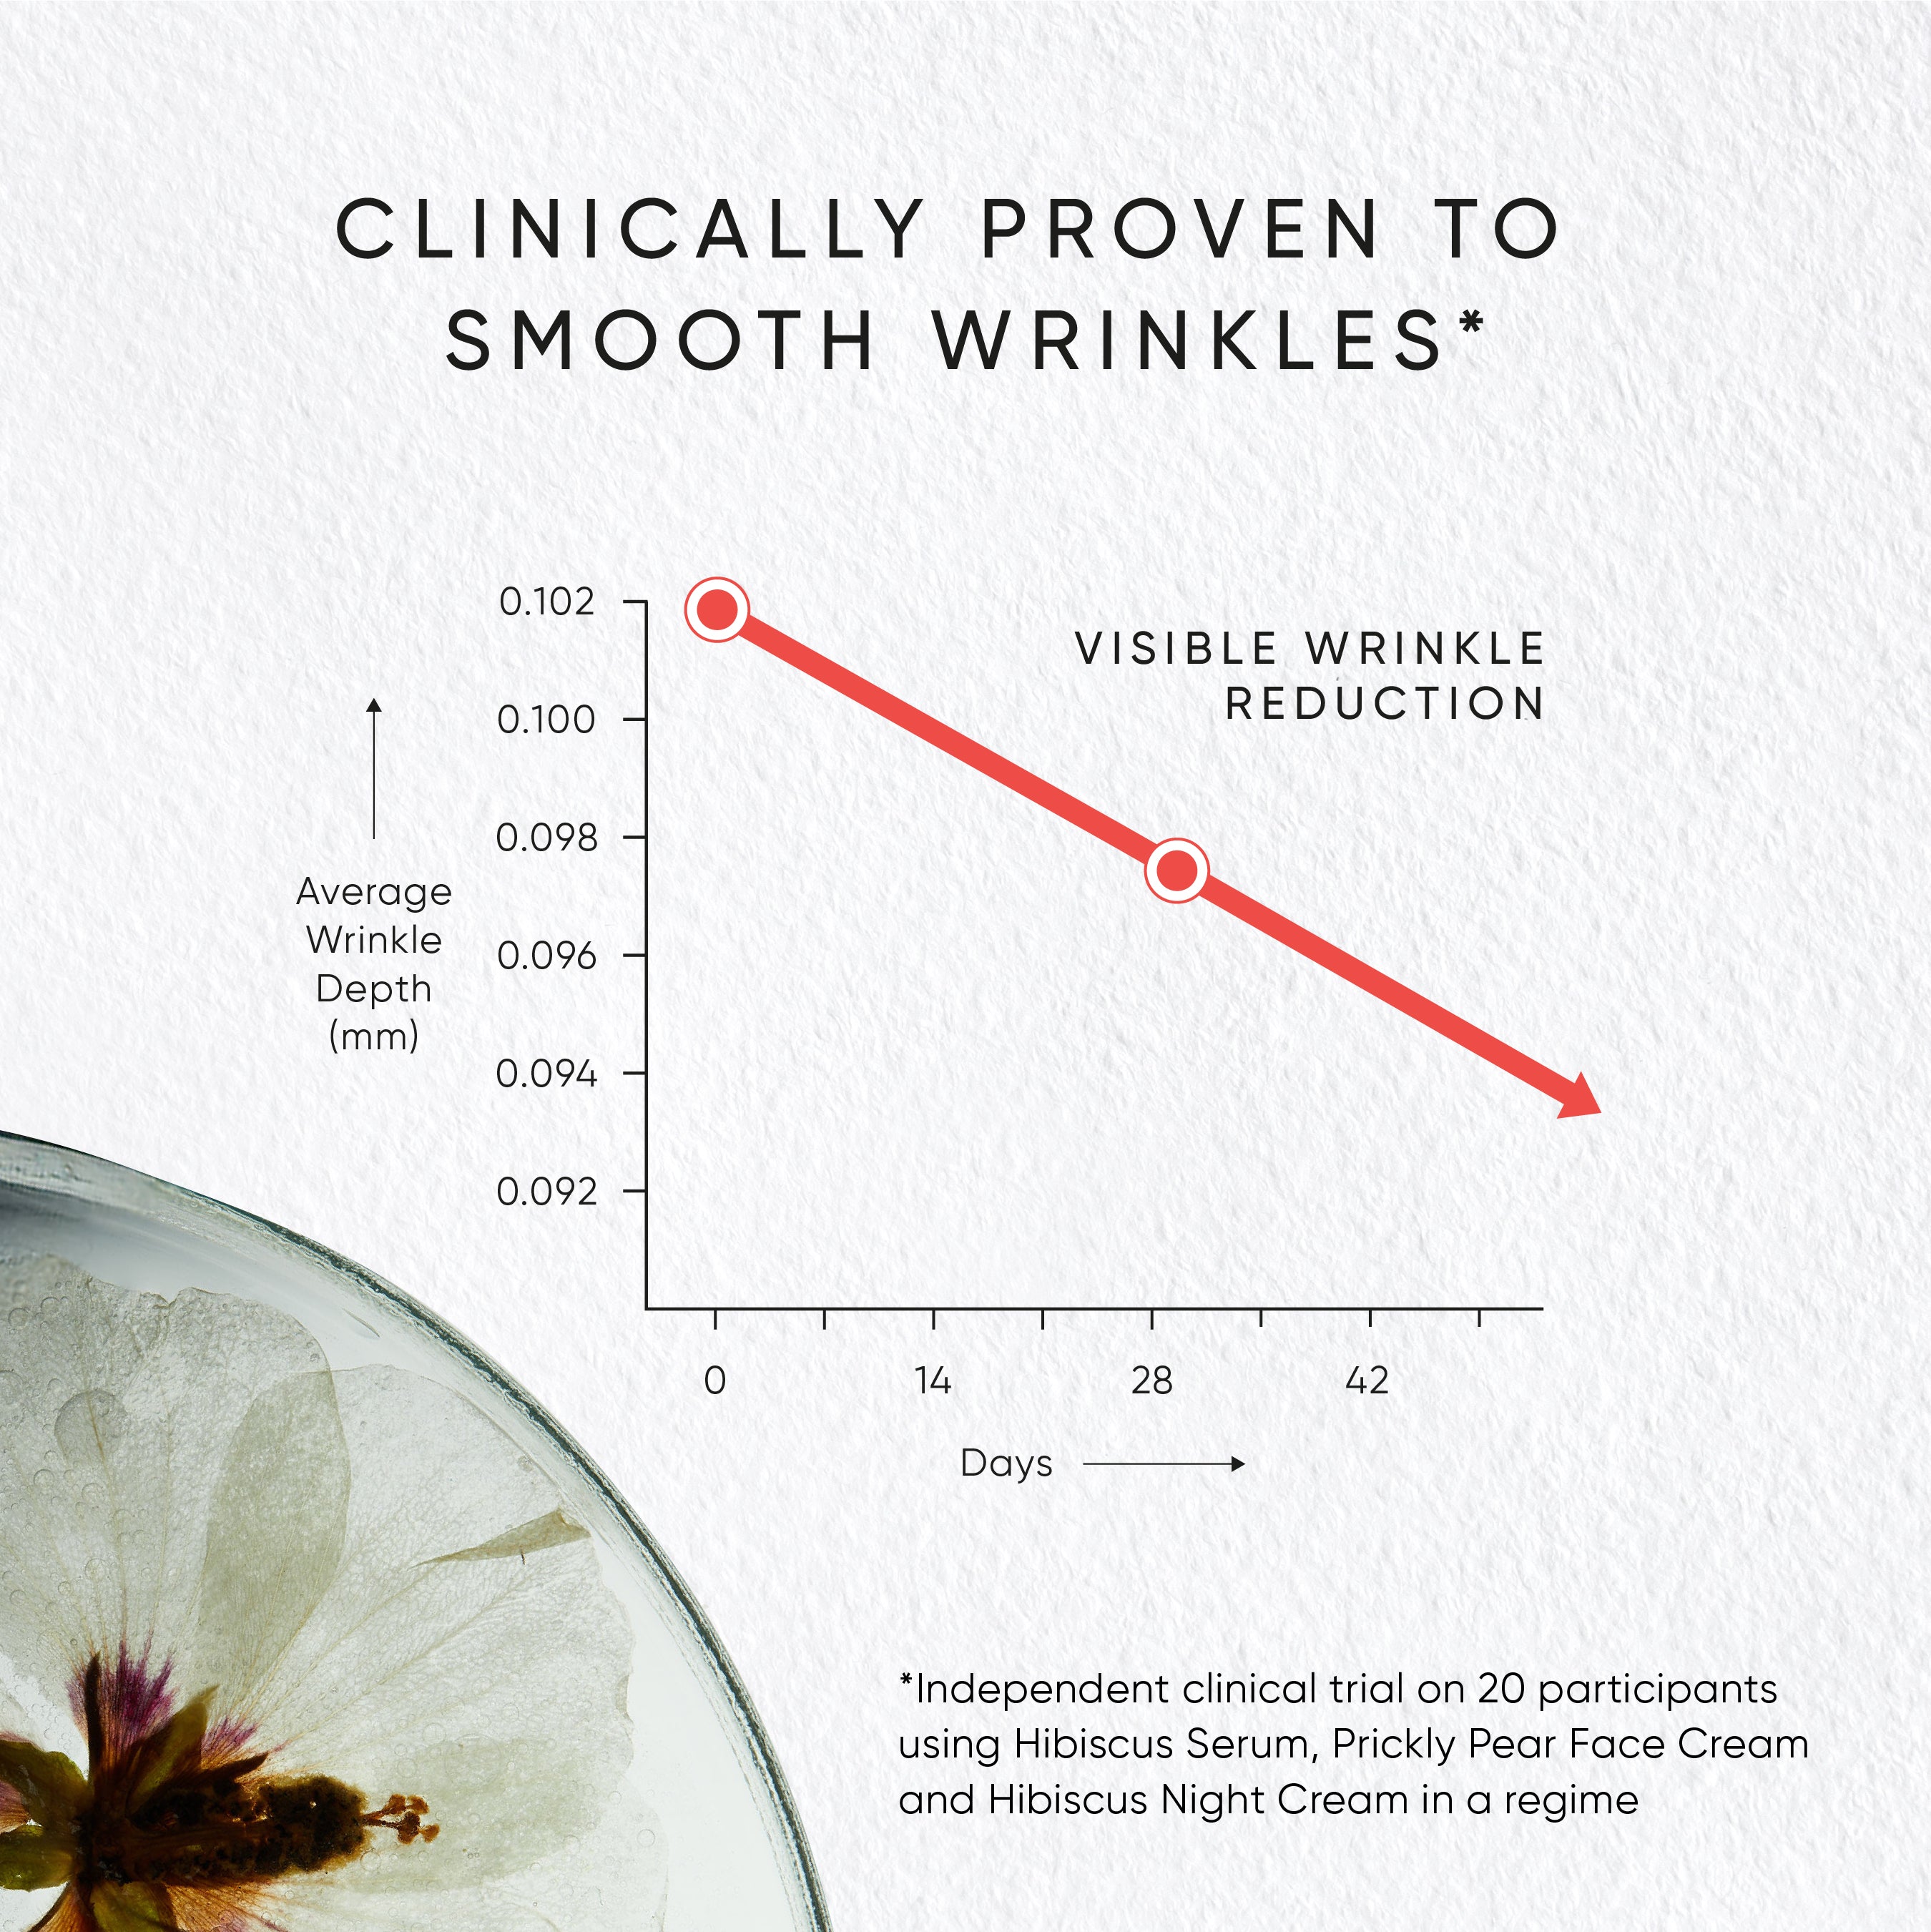

Clinically proven to smooth wrinkles when used in a regime with Hibiscus Serum and Prickly Pear Face Cream.

Clinically proven to smooth wrinkles thanks to neuropeptide Myoxinol™.

USER TRIAL RESULTS AFTER 4 WEEKS*

HYDRATION & MOISTURISATION

100% agree skin looks more hydrated.

95% agree skin feels deeply hydrated.

97% agree skin feels moisturised.

AGE-DEFYING

85% agree skin appears more youthful.

79% agree skin looks years younger.

75% saw a visible reduction in wrinkles.

81% saw a visible reduction in fine lines.

LIFTING & FIRMING

92% agree skin appears lifted.

88% agree skin elasticity improved.

85% agree skin appears plumper.

83% agree skin feels firmer.

HEALTHY & GLOWING

98% agree skin looks healthier.

98% agree skin feels nourished.

90% agree skin looks restored.

89% agree skin appears more glowing.

96% would recommend this product to friends.

*In a 4-week independent consumer trial on 81 participants.